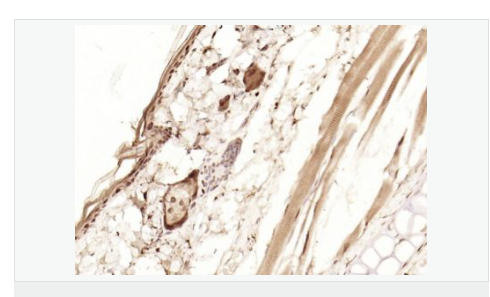

| 產(chǎn)品應(yīng)用 | WB=1:1000-2000 ELISA=1:1000-5000 IHC-P=1:100-500 IHC-F=1:100-500 Flow-Cyt=1ug/Test ICC=1:100-500 IF=1:100-500 (石蠟切片需做抗原修復) not yet tested in other applications. optimal dilutions/concentrations should be determined by the end user. |